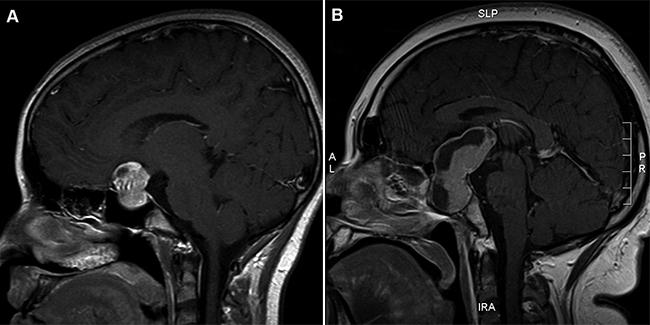

Nina de 15 anos de edad sin antecedentes morbidos. Tuvo su menarquia a los 14 anos, sin menstruaciones posteriores. Desde septiembre del 2008 nota disminucion progresiva de la agudeza visual, asociada a cefalea y galactorrea de 2 anos de evolucion. En marzo de 2009 se realiza campimetria que demuestra hemianopsia bitemporal y el oftalmologo detecta defecto pupilar aferente. La RM mostro un proceso expansivo selar y supraselar solido y quistico de 3 x 3 x 1,9 cm con extension hacia el seno cavernoso izquierdo, con desplazamiento y compresion del quiasma optico especialmente a derecha (Figura 1A). Al examen fisico destacaba hemianopsia bitemporal detectada por confrontacion. Eutrofica con ausencia de caracteres sexuales secundarios, incluido el vello axilar y pubiano (Tanner I). El desarrollo mamario era escaso (Tanner II) y no habia galactorrea. El estudio hormonal pre-operatorio mostraba prolactinemia muy elevada (1967 ng/mL) y calcemia 9,0 mg/dL (VN: 8,1-10,2 mg/dL) (Tabla 1). Se realiza cirugia descompresiva por via transcraneana con reseccion parcial del macroadenoma. La biopsia y el estudio inmunohistoquimico describen la lesion como prolactinoma que, de acuerdo al indice de proliferacion celular, se catalogo como adenoma hipofisiario anaplasico (Prl positiva en 95% de celulas, HGH, ACTH, TSH, FSH, LH negativos, Ki-67 positivo en 8 a 10% de los nucleos). Cursa el postoperatorio sin complicaciones y con recuperacion visual bilateral parcial. Es dada de alta con indicacion de cortisol 20 mg/d, levotiroxina 50 ug/d y cabergolina 0,5 mg 2 veces/semana.

Hombre de 23 anos de edad, sin antecedentes morbidos. Consulta en octubre del 2008 en nuestro hospital por aumento de peso no cuantificado en los ultimos anos, asociado desde hacia un ano a cefalea referida principalmente a la zona interciliar, con disminucion de la vision del ojo izquierdo. Inicio su pubertad a los 14 anos. Al examen fisico destaco la talla baja con proporciones corporales mantenidas, y actitud y voz infantil. La campimetría por confrontación demostró disminución de visión temporal derecha y abolición casi total del campo visual izquierdo. Tenía obesidad de predomino central, con IMC 37, piel gruesa y fría, con vello muy escaso a nivel de genitales (Tanner III). El pene era pequeño (2,5 cm) y los testículos aparecían con buen desarrollo (Tanner IV), sin galactorrea ni ginecomastia. El estudio hormonal pre operatorio demostró: prolactinemia de un “pool” 3177 ng/mL y calcemia 9,7 mg/dL (VN 8,1 -10,2 mg/dL) (Tabla 1) El estudio con TAC y RM selar demostraron una gran lesión expansiva intra y supraselar con carácter sólido-quístico que alcanzaba el tercer ventrículo, comprimiendo el quiasma óptico y la región hipotalámica. No se observaron signos de hidrocefalia (Figura 1B). Se planteó el diagnóstico de prolactinoma gigante con compromiso visual avanzado y grave, ya que en la evaluación oftalmológica se encontraron papilas levemente pálidas en el ojo izquierdo y menos rosada en el ojo derecho, especialmente en la zona temporal. Se constataron defectos de visión heterónimos bitemporales. Se realizó cirugía hipofisisaria por vía transesfenoidal, evolucionando sin complicaciones y con recuperación parcial de la visión del ojo izquierdo. La biopsia y el estudio inmunohistoquímico demostraron un prolactinoma que, de acuerdo al índice de proliferación celular se catalogó como adenoma hipofisiario atípico (Prl positiva en 100% de células, HGH, ACTH, TSH, FSH, LH negativos, Ki-67 positivo en 3 a 4% de los núcleos). Fue dado de alta con cabergolina 0,5 mg 2 veces/ semana y levotiroxina 100 ug/d.

Figura 1. RM (secuencia T1) de la región selar de casos 1 (A) y 2 (B).